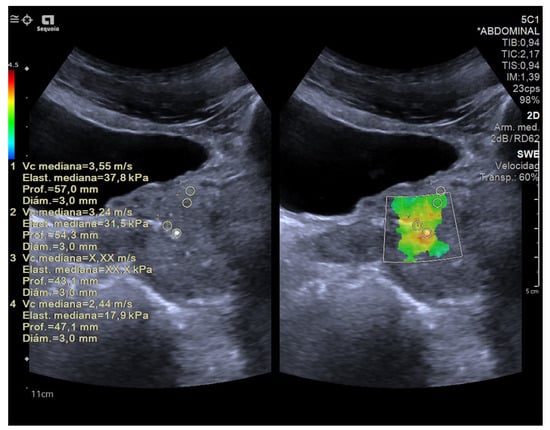

4.3. Elastography in Testicular Lesions